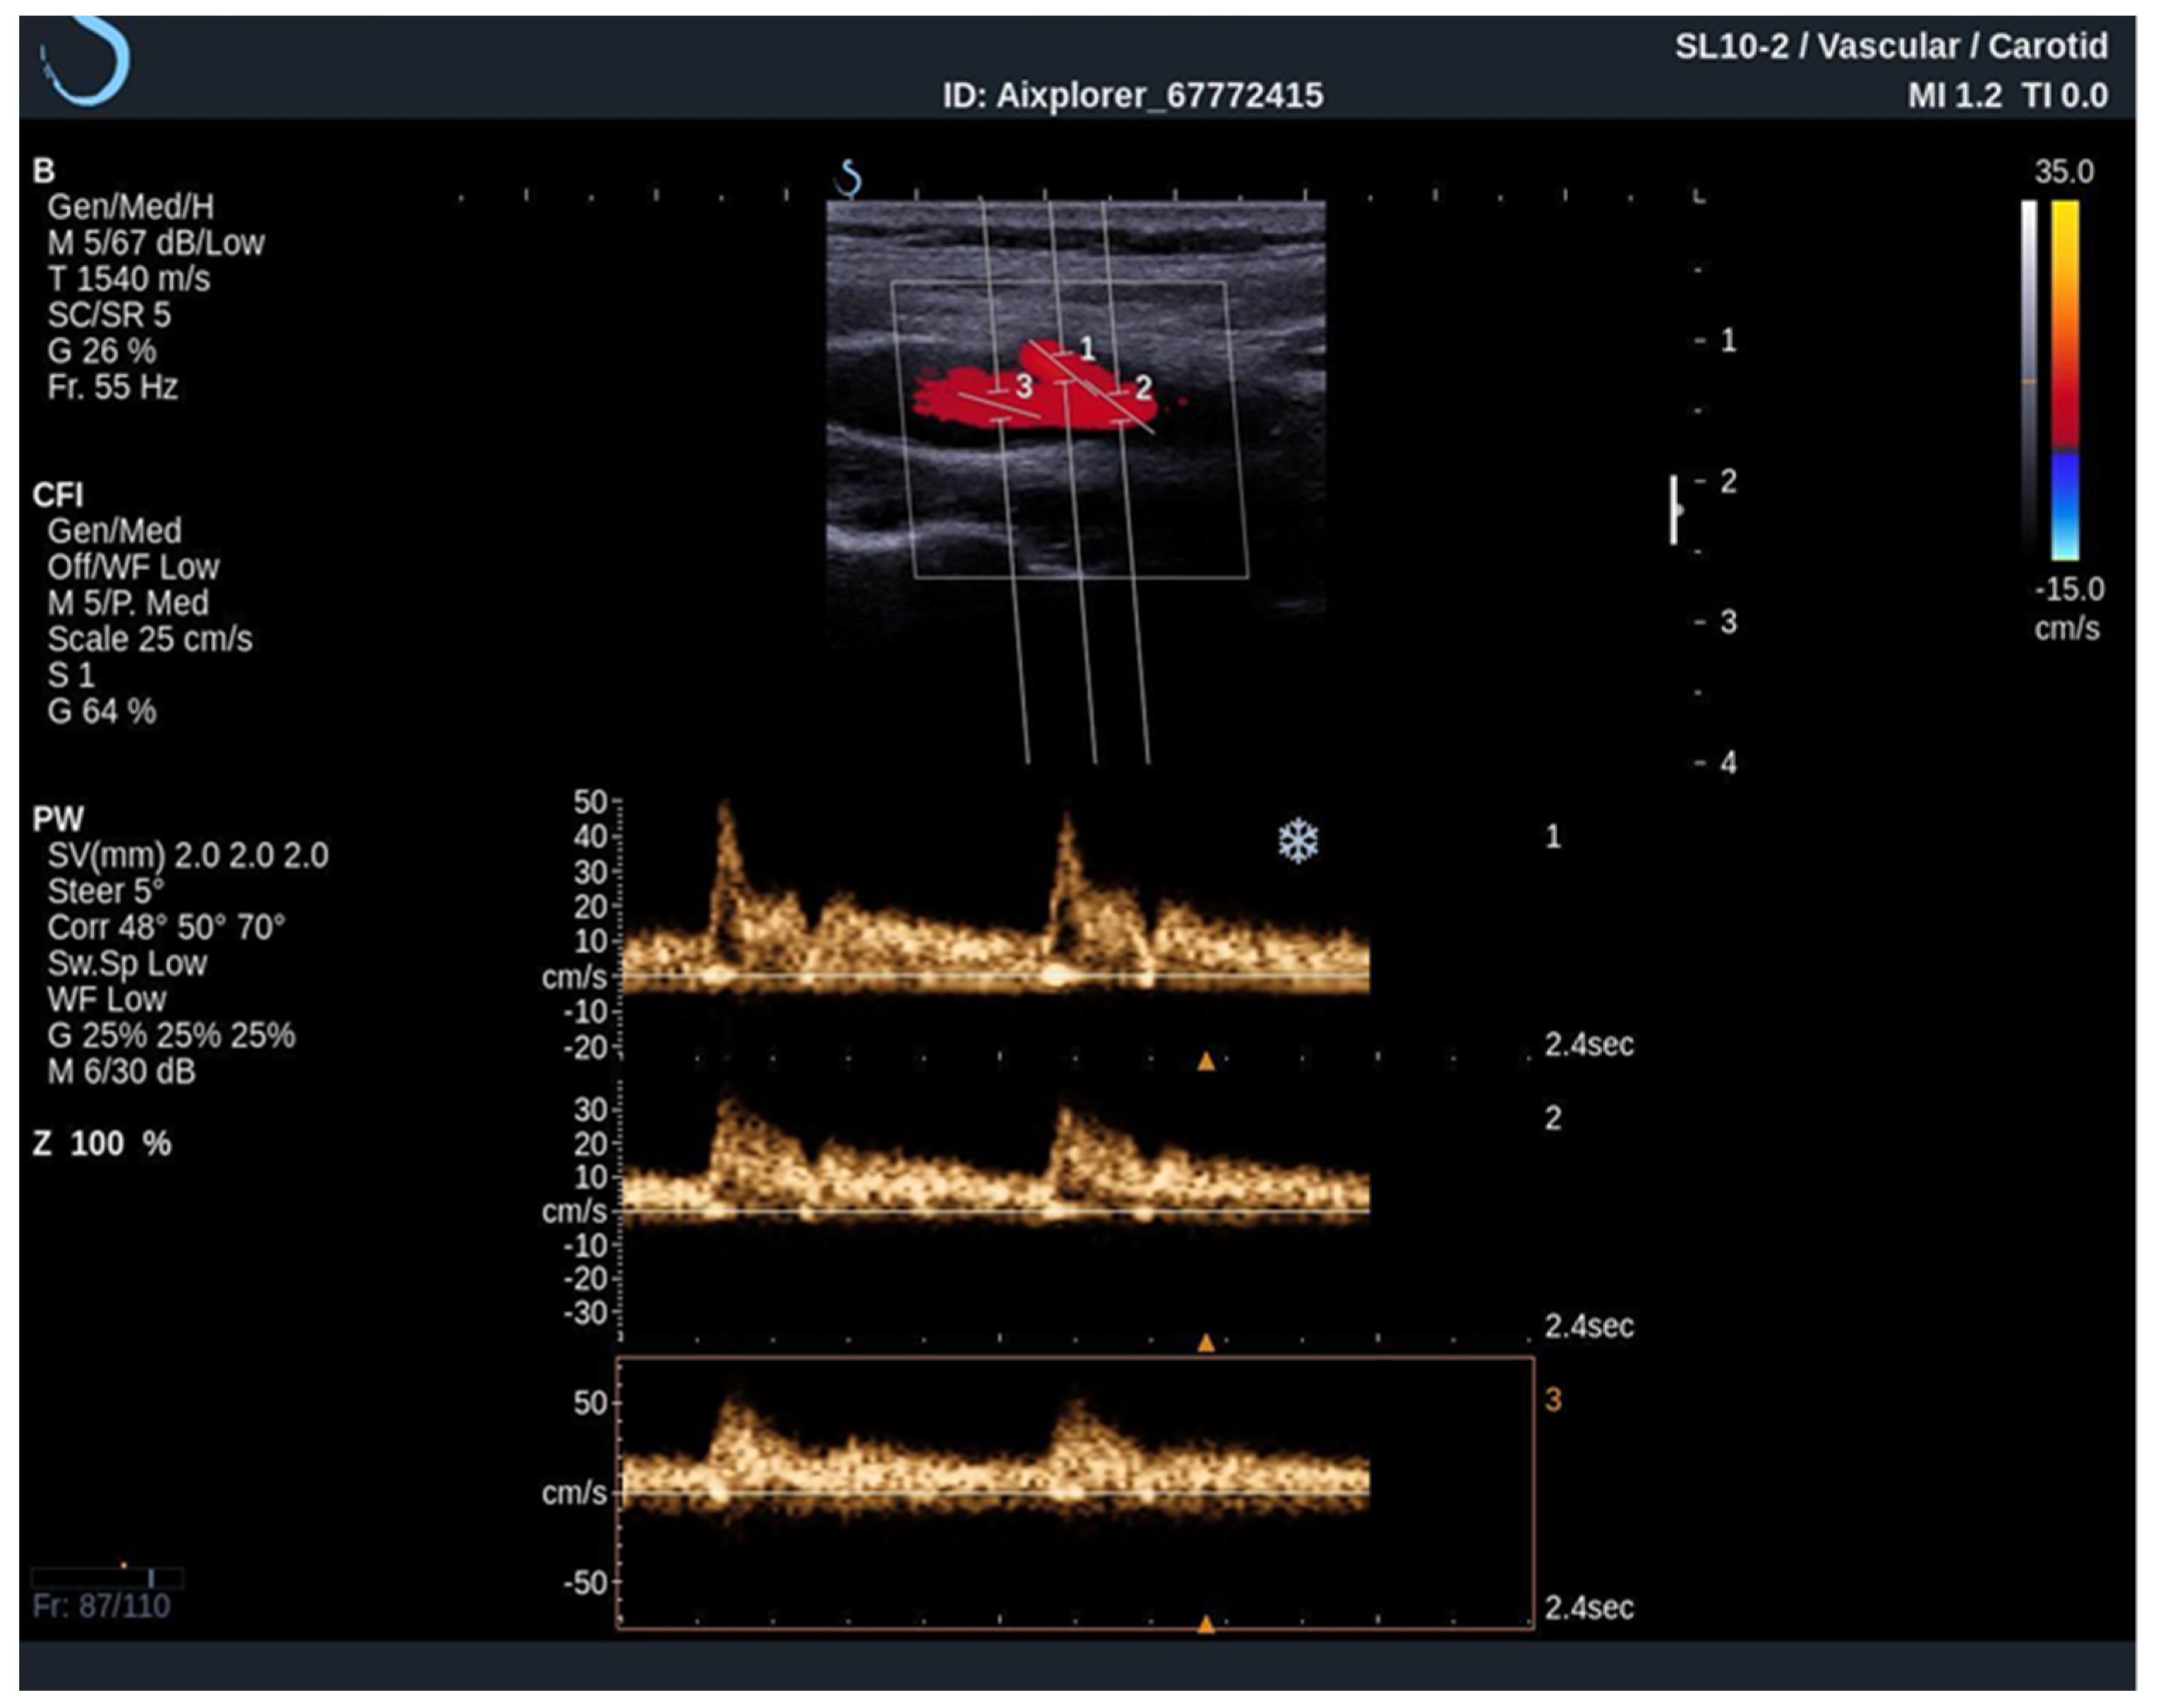

To acquire data from these modes, the practitioner switches between them analyzing the PW Doppler at the locations pinpointed by the color Doppler image. With the introduction of UltraFast™ Doppler (SuperSonic Imagine, Aix en Provence, France), quantitative data can be assessed in all pixels at the same time. Because it relies on plane waves and not focused beams in the image acquisition, there is no time lag at the sides of the image. On a conventional ultrasound device, such quantitative analysis is only possible by limiting the region of interest (ROI) to a single acoustic line. UltraFast™ Doppler allows the merging of CFI and PW Doppler mode in a single acquisition (Figure 3).

When performing an UltraFast Doppler examination, a single-shot acquisition mode is usually initiated from the conventional color Doppler imaging mode. After that, a range of UltraFast Doppler data is acquired (typically 2 to 4 s), and the picture is frozen. The examiner can then review the UltraFast color flow data, review a single or multiple frames offering the best image visualization of the flow characteristics of interest and simultaneously perform a retrospective spectral analysis of the color box. Furthermore, using UltraFast™ Doppler, a short clip of not only one, but multiple regions of interest can be obtained, providing a more precise comparison of both mean and peak flow velocity originating from the same cardiac cycle (Figure 4) [21].

Figure 4. An UltraFast™ Doppler examination of the bifurcation of the carotid artery. Several measurements can be performed independently of each other with a high degree of reliability since the acquisition is made during the same cardiac cycle. In this example, spectra from the ICA (3) and ECA (2) are analyzed simultaneously, one can differentiate the ICA from the ECA on the basis of spectral morphology with ECA demonstrating a high-resistance spectrum and the ICA demonstrating a low-resistance spectrum.